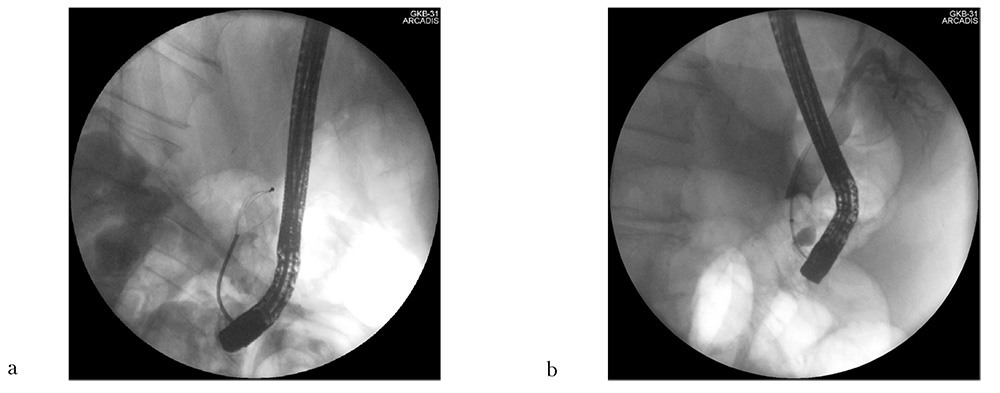

После этого с помощью механического литотриптора фирмы Boston Scientific (США) диаметром 3 см наибольший фрагмент камня был успешно захвачен и разрушен, а все остальные части и осколки раздробленного лазером конкремента без технических трудностей удалены с помощью корзинки Дормиа и экстракционного баллона. При контрольной обтурационной холангиографии с использованием раздутого ревизионного баллона была констатирована полная санация билиарного тракта (рис. 6).

Рис. 6: a — механическая литотрипсия наиболее крупного фрагмента конкремента после лазерной литотрипсии (холангиограмма); b — контрольная ревизия экстракционным баллоном с выполнением обтурационной холангиографии (холангиограмма)